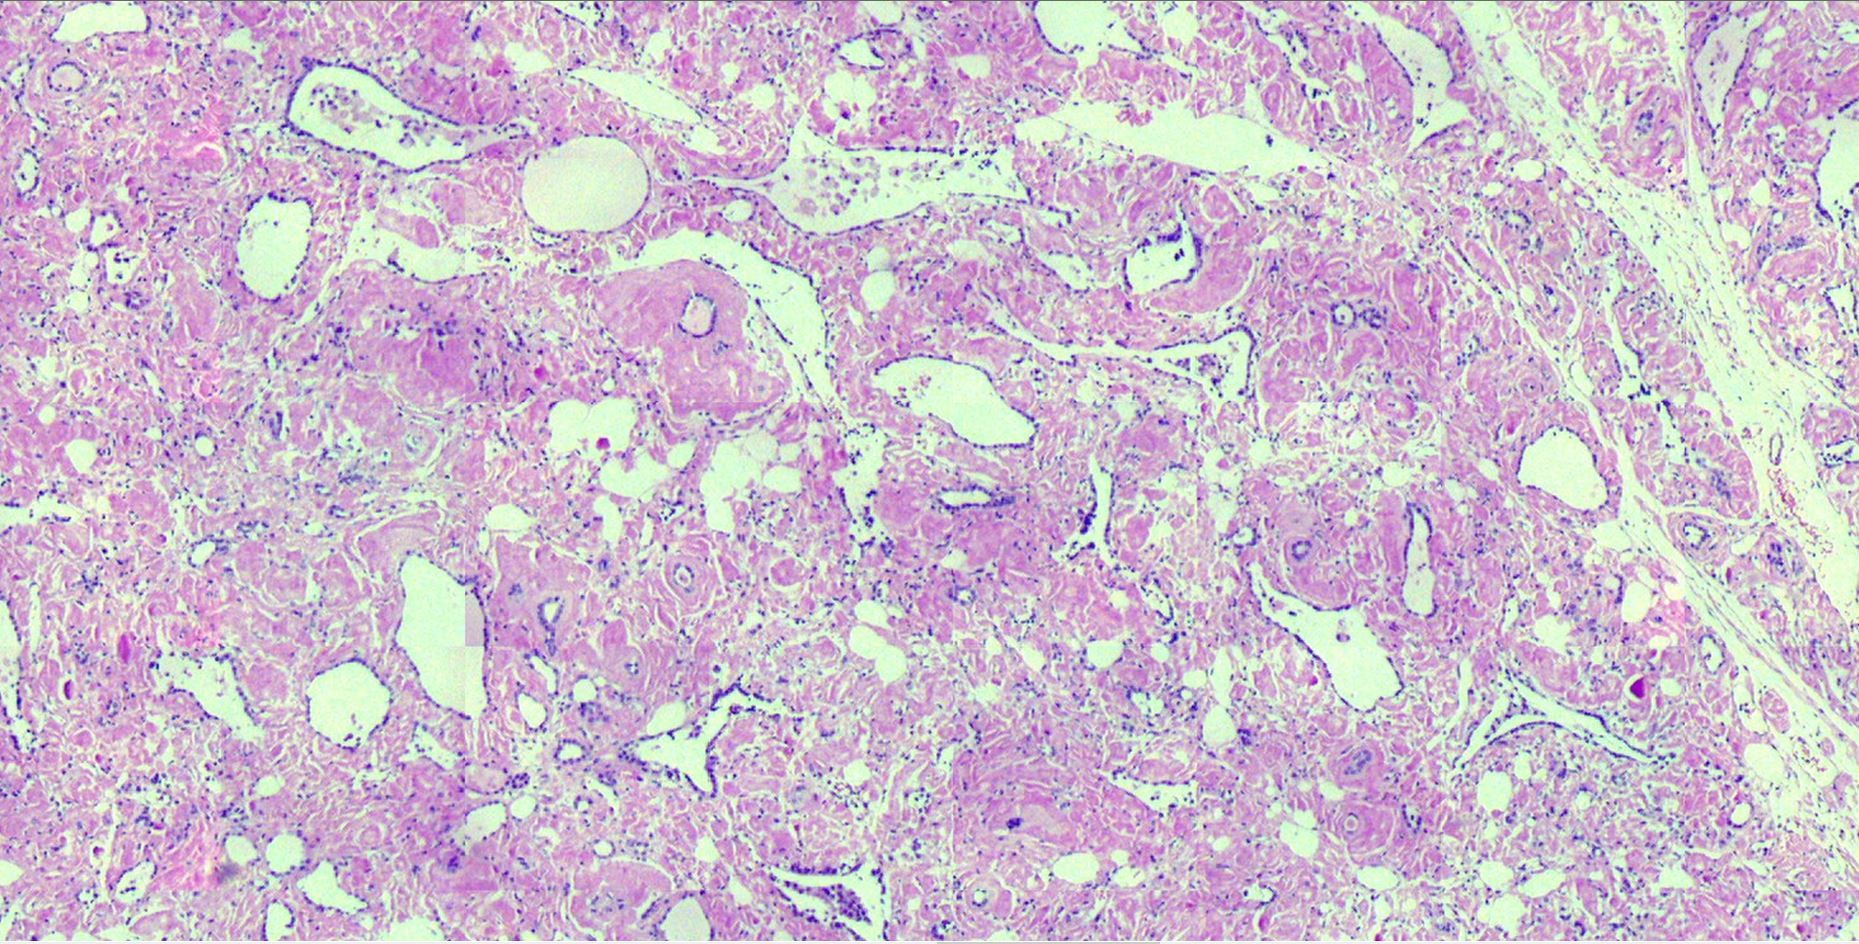

Piyano tuşlu böbrek tümörü Clear cell papillary renal cell tumor. Nuclei are piano key appearance **Note:** Tiles are generated locally and included in the repository. Manually commit and push to GitHub to make the viewer work.